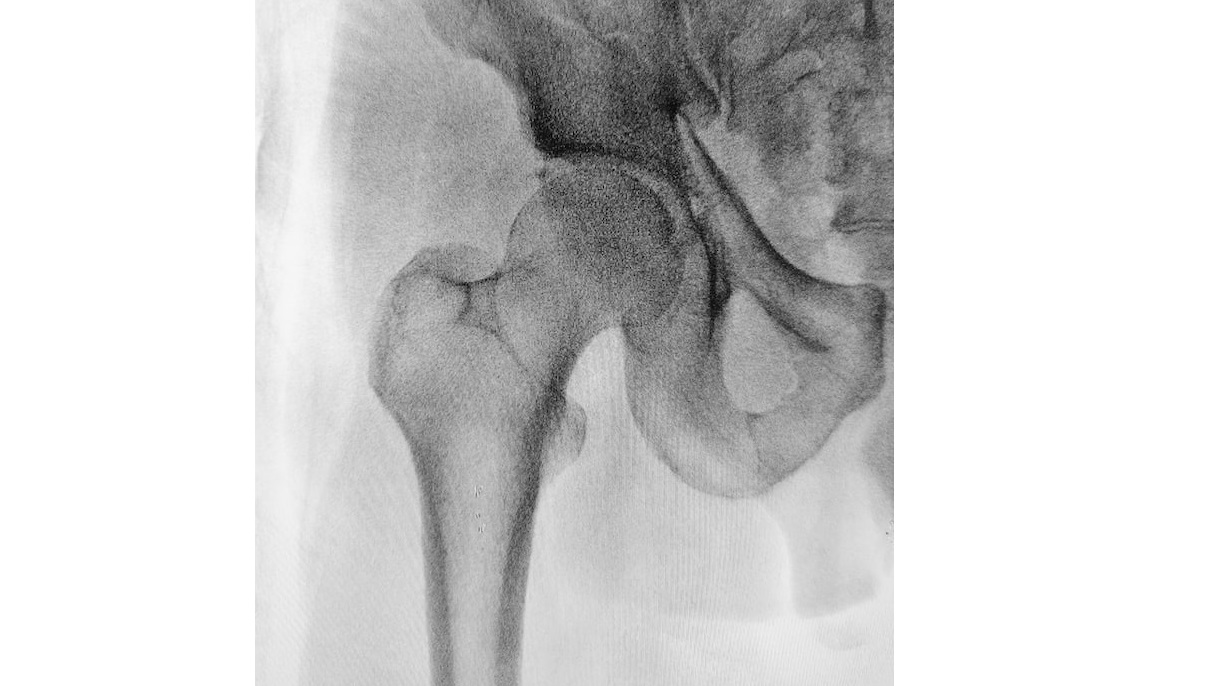

Foto de Mehmet Turgut Kirkgoz en Unsplash

El adelanto de la cirugía mediante una estrategia para determinar la función plaquetaria en pacientes que han sufrido una fractura de cadera y están con tratamiento antiagregante es seguro. Los resultados de un ensayo clínico que comparó esta estrategia con el tratamiento habitual (la cirugía diferida) muestran que no hubo diferencias entre los pacientes tratados con cirugía precoz o tardía, según se refleja en un reciente artículo en el Journal of Clinical Medicine.

“Tras un seguimiento de 12 meses, hemos comprobado que es seguro acortar el tiempo de espera hasta la cirugía bajo anestesia neuroaxial aplicando una estrategia de determinación de la función plaquetaria en pacientes con una fractura proximal de fémur”, explica la investigadora que ha liderado este estudio, María José Martínez Zapata, investigadora del CIBERESP en el Centro Cochrane Iberoamericano y el Instituto de Investigación del Hospital Sant Pau de Barcelona. “La calidad de vida mejora en los primeros seis meses después de la cirugía sin diferencias entre los grupos comparados”, añade.